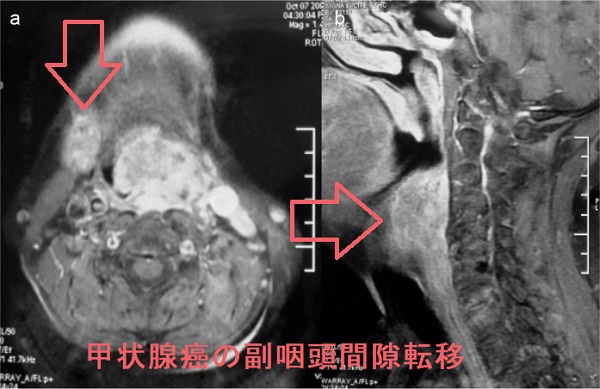

若年性血管線維腫は放射線治療が行われ放射線誘発性甲状腺がんの問題があった。喉頭乳頭腫はヒトパピローマウイルス(HPV)感染が原因の良性腫瘍だが稀に癌化。甲状腺乳頭癌の副咽頭間隙転移、下咽頭転移はまれ。喉頭癌・下咽頭癌(扁平上皮癌)の甲状腺転移がある。上咽頭扁平上皮がんはヘルペスウイルスの一種、EBウイルス(エプスタイン・バールウイルス)が主な原因。未分化扁平上皮がんが多く、放射線感受性が高いため放射線根治治療になり、放射線甲状腺炎や放射線唾液腺炎の合併症・後遺症が生じる。

若年性血管線維腫(juvenile angiofibroma)は10-18歳の男子に多く、上咽頭に好発する極めて血管豊富な良性腫瘍で、成人すると増殖が止まります。良性腫瘍なのに、局所浸潤が強く、再発率も高いのが特徴です。